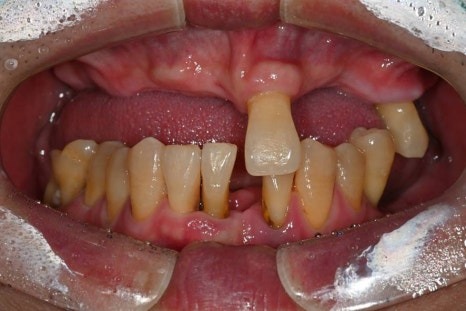

이번에 소개해드릴 환자분은

당뇨와 고혈압, 두 가지 전신질환을

모두 가지고 계셨던 분으로

치아 결손이 광범위해

전악 임플란트가 필요한 상황이었습니다.

· 상악은 잇몸뼈가 매우 얇고 치아가 거의 남아 있지 않은 상태

· 하악은 부분 결손과 앞니의 심한 동요

· 식사가 어려울 정도로 기능 저하가 심한 상태